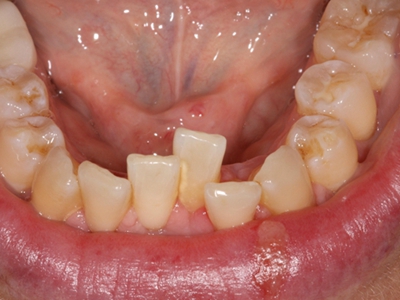

阻生牙是指由于邻牙、骨或软组织的阻碍而只能部分萌出或完全不能萌出,且以后也不能萌出的牙。引起牙阻生的成因,主要是由于颌骨缺乏足够的空间容纳全部恒牙。常见的阻生牙为下颌第三磨牙、上颌第三磨牙及上颌尖牙。

阻生牙可反复引起冠周炎,或引起邻牙牙根吸收和破坏,位置不正,不能完全萌出,好发部位是上、下颌第三磨牙。

发育正常的牙齿同时正畸治疗又不需要进行拔牙矫治,通常需要对阻生牙进行牵引治疗,引导进入牙弓,而对于发育异常的阻生牙加之正畸治疗需要进行拔牙矫治,通常可以考虑将阻生牙拔除,而避免再拔发育正常的前磨牙,即降低了正畸治疗的难度及不确定性,又保留了相对正常的牙齿。